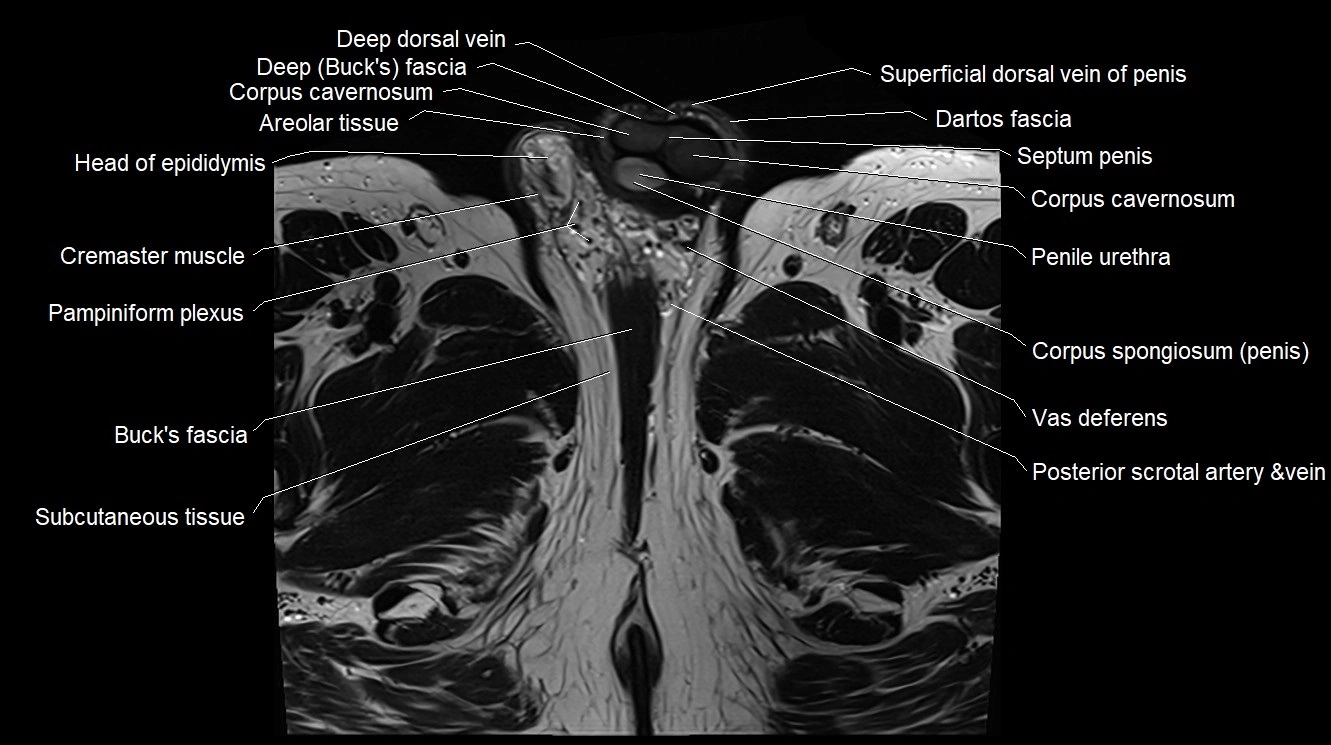

MRI image